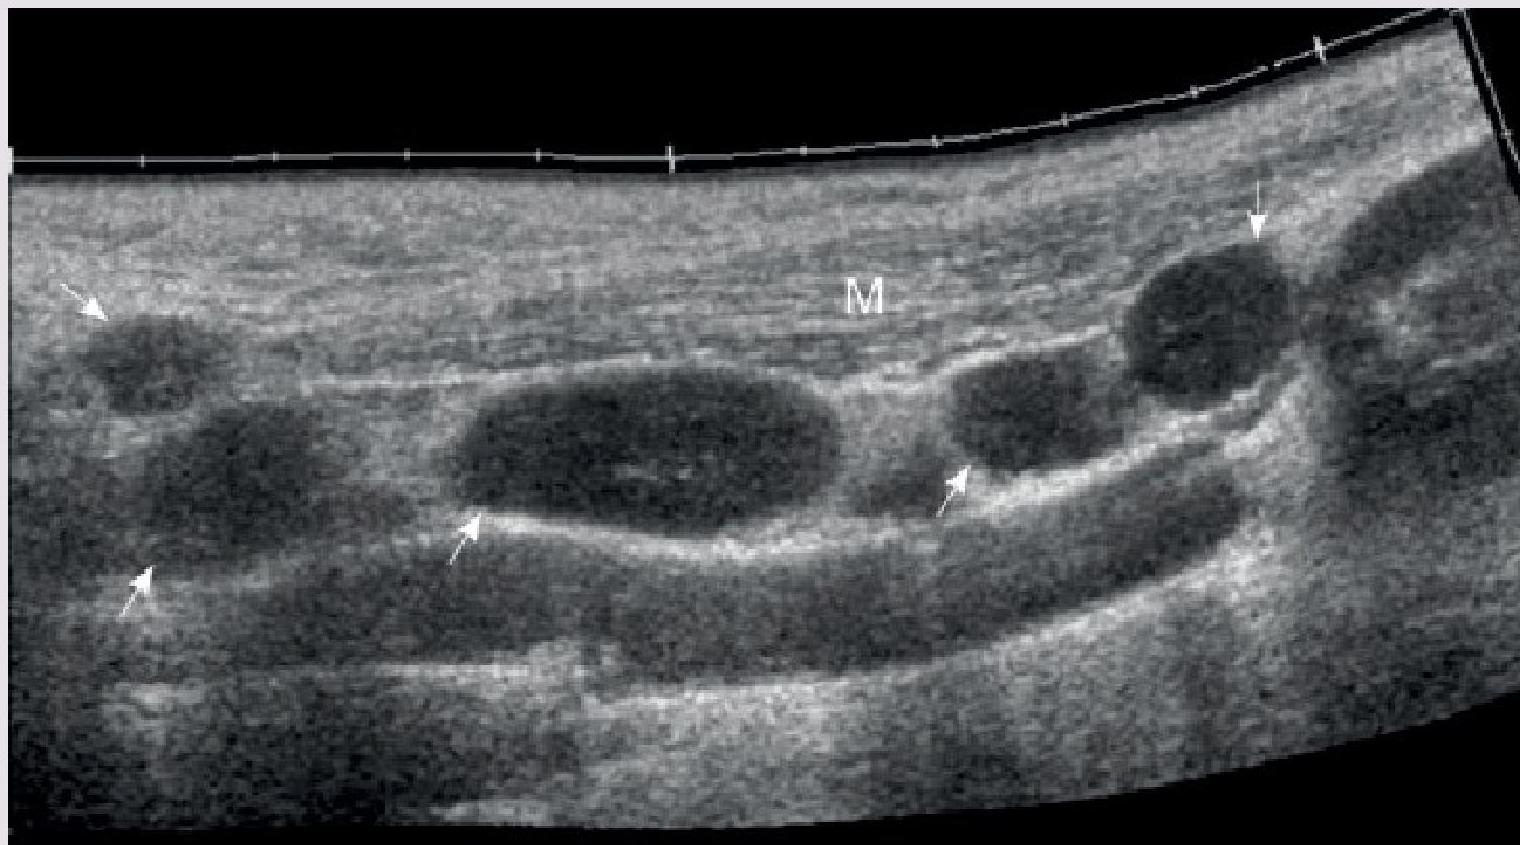

- Ultrasound of the lymph node

Multiple enlarged lymph nodes (arrows) along the sternocleidomastoid muscle (M) Z